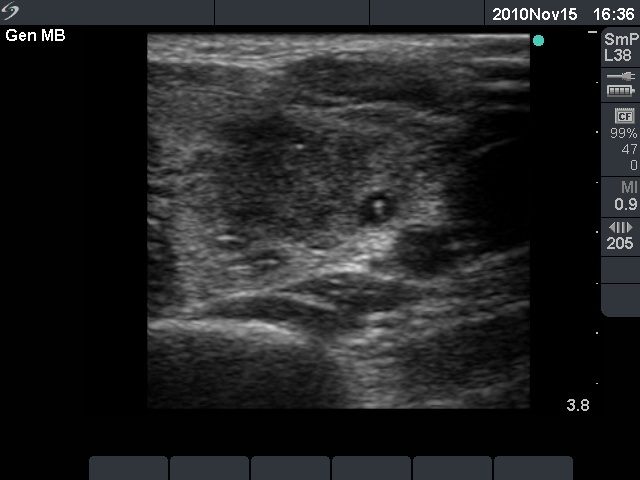

Initial examination (first row of images):

Ultrasonography: The right thyroid was echonormal and contained several small, insignificant lesions. There was a hypoechogenic lesion with blurred borders in the central and in the ventro-medial part of the left thyroid with increased intranodular blood flow.